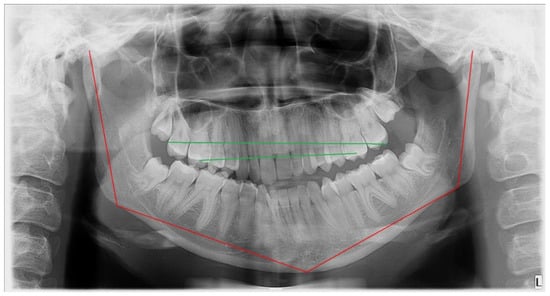

M—maxillary bones; low downward position of the maxilla on the affected side. Maxillary compensatory down growth = with or without maxillary cant deviated horizontal (transverse) occlusal plane (Figure 3), also manifested as the asymmetrical position of part of the maxillary bone with or without sinus floor;

Figure 3. Maxillary compensatory down growth on the affected side.